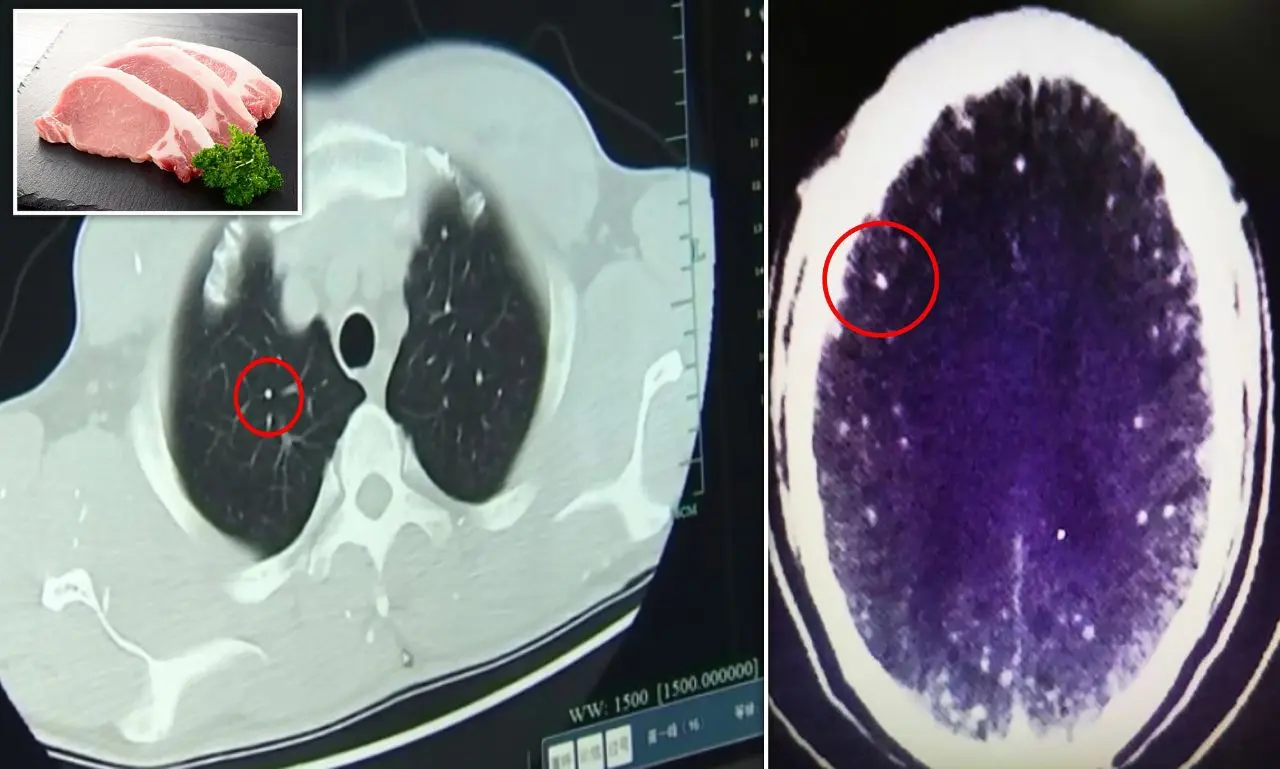

และเมื่อเขาถูกนำส่งโรงพยาบาลในเครือของคณะแพทยศาสตร์มหาวิทยาลัยเจ้อเจียง แพทย์ได้ทำการสแกนสมองและหน้าอก โดยการใช้คลื่นแม่เหล็กไฟฟ้า (MRI) และแพทย์ได้ตรวจพบว่าสมองและหน้าอกของนาย Zhu นั้นเต็มไปด้วยซิสต์ของพยาธิตัวตืดหมู

นอกจากนี้ ดร. หวาง ยังเปิดเผยว่า นาย Zhu ยังมีซีสต์ในปอดและกล้ามเนื้อหน้าอกด้วย คาดว่าน่าจะมีพยาธิตัวตืดบมากกว่า 700 ตัว ในร่างกาย รวมถึงสมองและปอด